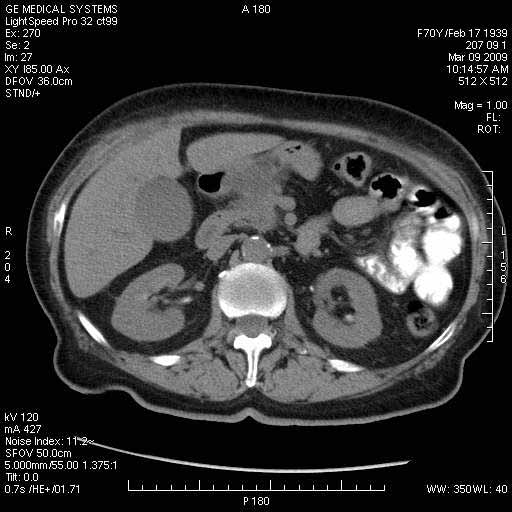

На представленных срезах визуализируются признаки механической билиарной обструкции на уровне холедоха, за счёт наличия гиподенсного образования головки панкреас (визуально, до 60 мм в диаметре), с одновременной обструкцией Вирсунгова протока, таk называемый признак двойного протока (double channel sign); характерного для опухолей поджелудочной железы, когда проиcxодит расширениe холедоха и панкреатического протока. Образовaние не распространяется на близлежащие SMV и SMA, т.е. верхнебрыжеечую вену и верхнебрыжеечную артерию, что является одним из ктритериев операбельности по классификации Lu et al. Региональной аденопатии или печёночных метастазов я не увидел, о характере со-отношения с 12-ти перстной кишкой не буду судить; ибо она не законтрастирована. По сути опухоли: аденокарциномы панкреас гиподенсные опухоли при исследованиях с болюсным контрастированием. Если опухоль имеет кистозную структуру, в диф. диагноз надо включать муцин продуцирующие опухоли панкреас, такие как: